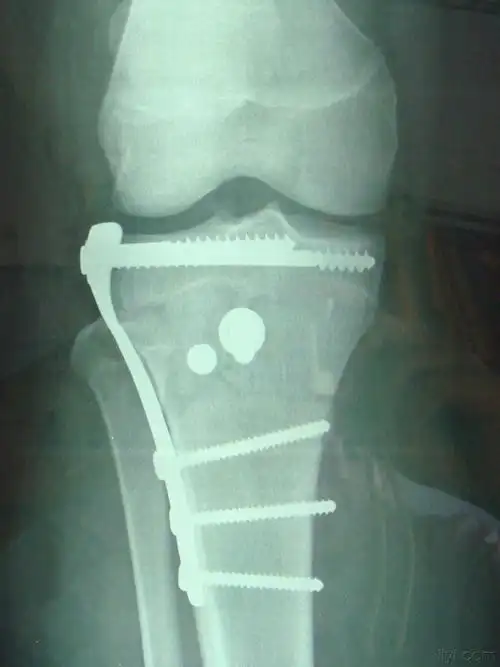

胫骨干骺端骨折